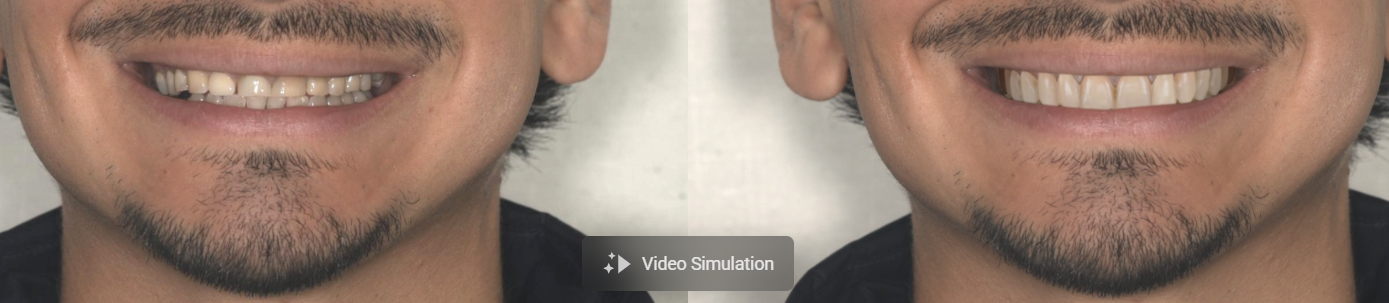

- fotók készítése a tervezéshez (mosolytervezés)

A legtöbb esetben a páciens már a műtét napján ideiglenes, rögzített fogpótlást kap.

Ez segít abban, hogy a páciensünk magabiztosan mosolyoghasson, beszélhessen, illetve rághasson.

Természetes megjelenés

A modern fogpótlások anyaguknak köszönhetően rendkívül esztétikusak és természetes hatásúak.

A modern implantológiai technológiáknak köszönhetően sok páciens már a műtét napján rögzített ideiglenes fogsort kap, így gyorsan visszanyerheti mosolyát, önbizalmát és a régi életét.